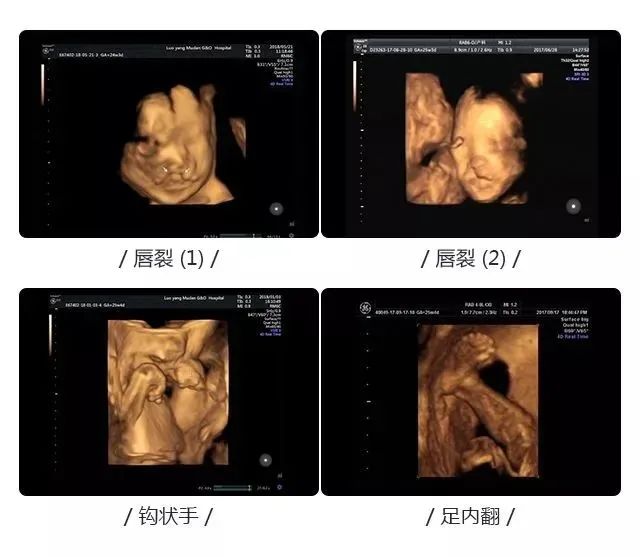

孕期检查:产前超声检查

超声影像(四维彩超)与一般超声检查相比,超声影像(四维彩超)在超声诊断方面具有四维图像成像速度快、图像清晰、分辨率高等优势,能够多方位、多角度观察宫内胎儿生长发育情况,为早期诊断胎儿先天性体表畸形和先天性心脏疾病提供更为准确的依据 相对于普通B超只能检查出胎儿的部分生理指标,超声影像(四维彩超)能够对胎儿进行较系统、全面的检查。